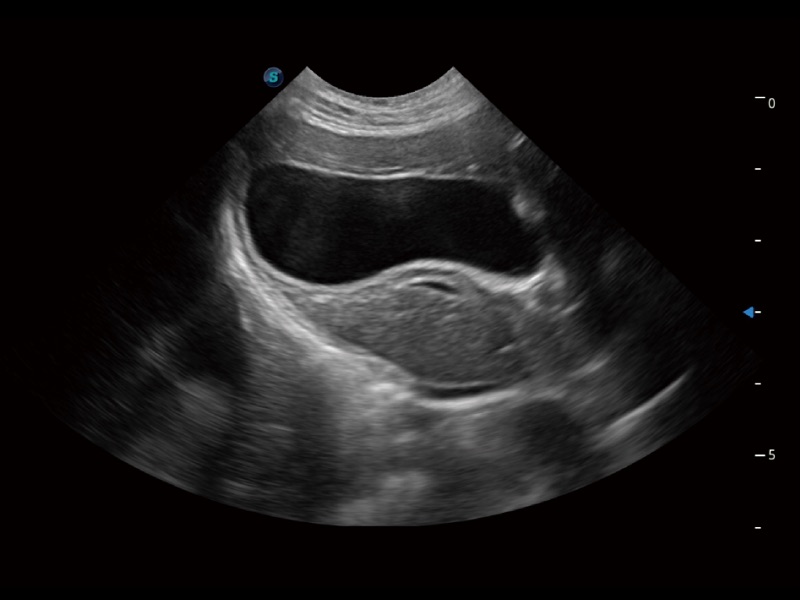

ProPet 70 進(jìn)一步提升了微米成像算法,更加注重對(duì)基礎(chǔ)原始圖像的還原和保留,在有效減少斑點(diǎn)噪聲、增強(qiáng)組織邊界顯示的同時(shí),避免過(guò)度優(yōu)化丟失真實(shí)的解剖信息。

ProPet 70專為動(dòng)物醫(yī)生設(shè)計(jì),對(duì)不同的動(dòng)物體型和生理結(jié)構(gòu)作出了針對(duì)性的優(yōu)化。通過(guò)動(dòng)物影像專用軟件,可滿足個(gè)性化的應(yīng)用需求,幫助動(dòng)物醫(yī)生獲得更精確的診斷數(shù)據(jù)。

為精細(xì)結(jié)構(gòu)及組織邊緣提供高清晰度的圖像和更大的成像視野。幫助減輕醫(yī)生的用眼疲勞,快速精準(zhǔn)獲得測(cè)量的數(shù)據(jù)。